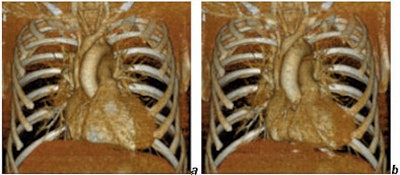

![]() |

| Cardiac images reconstructed from a gated chest CT obtained with a collimation of 40 x 0.625 mm and a dose of CTDIvol = 20 mGy. Reconstructions (a) in diastole, (b) in systole. Images courtesy of Dr. Mathias Prokop. |

A four-slice scanner could already produce functional information from the heart. The new scanner generation makes it possible to combine evaluation of the lungs with evaluation of heart function without having to increase the dose substantially compared to a standard chest CT. And noise can be controlled more easily in functional imaging exams compared to standard cardiac imaging. This is also the reason why late-enhancement exams are possible with less than 1 mSv of radiation, Prokop said.

"You can take cardiac function from any chest CT because you can now easily cover the whole chest," he said. "You can do integral analysis of the aorta and the coronaries, and you can analyze cardiac function."